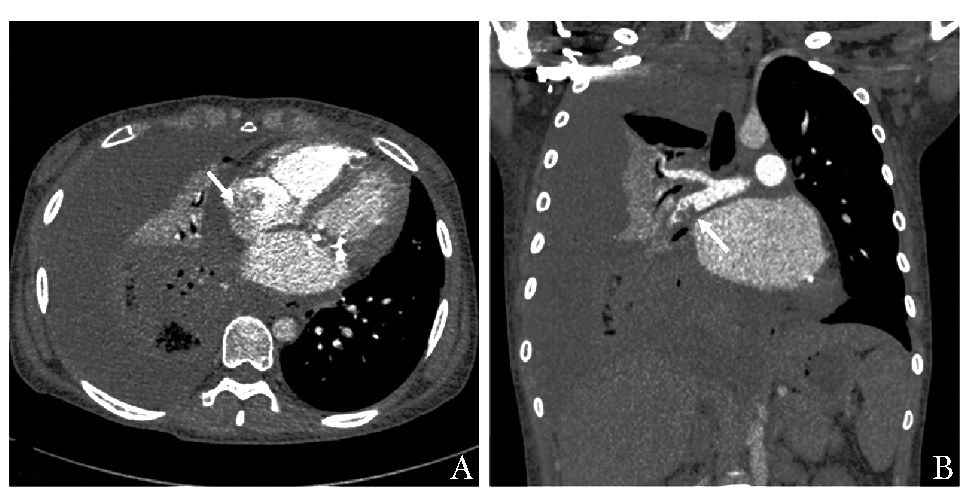

摘要: 心腔内血栓形成是系统性红斑狼疮(systemic lupus erythematosus,SLE)继发抗磷脂综合征(antiphospholipid syndrome,APS)的罕见并发症,治疗难度极大。本文报道1例SLE合并心内血栓、肺栓塞病例,病情复杂,猝死风险高,血栓和出血状态下的抗凝选择、感染状态下的原发病评估和治疗均较为棘手。经过多学科诊疗,在内科积极治疗的基础上,创造手术条件并选择恰当时机完成手术治疗,病情得到有效控制。Abstract: Intracardiac thrombus is a rare complication of Antiphospholipid syndrome secondary to systemic lupus erythematosus (SLE). Its treatment is extremely tough and requires a multidisciplinary approach. We reported a case of SLE with intracardiac thrombus and pulmonary embolism. The patient was complicated with hemoptysis and kidney injury, and had a high risk of sudden death from incidental thrombus shedding off. In the state of thrombosis and hemorrhage, the management of anticoagulation and the evaluation and treatment of the primary disease complicated with infection are challenging. The multidisciplinary collaboration helpedus to create a more favorable surgical condition while controlling SLE aggressively. After surgical treatment at the proper time, the outcome of the patient was satisfying.